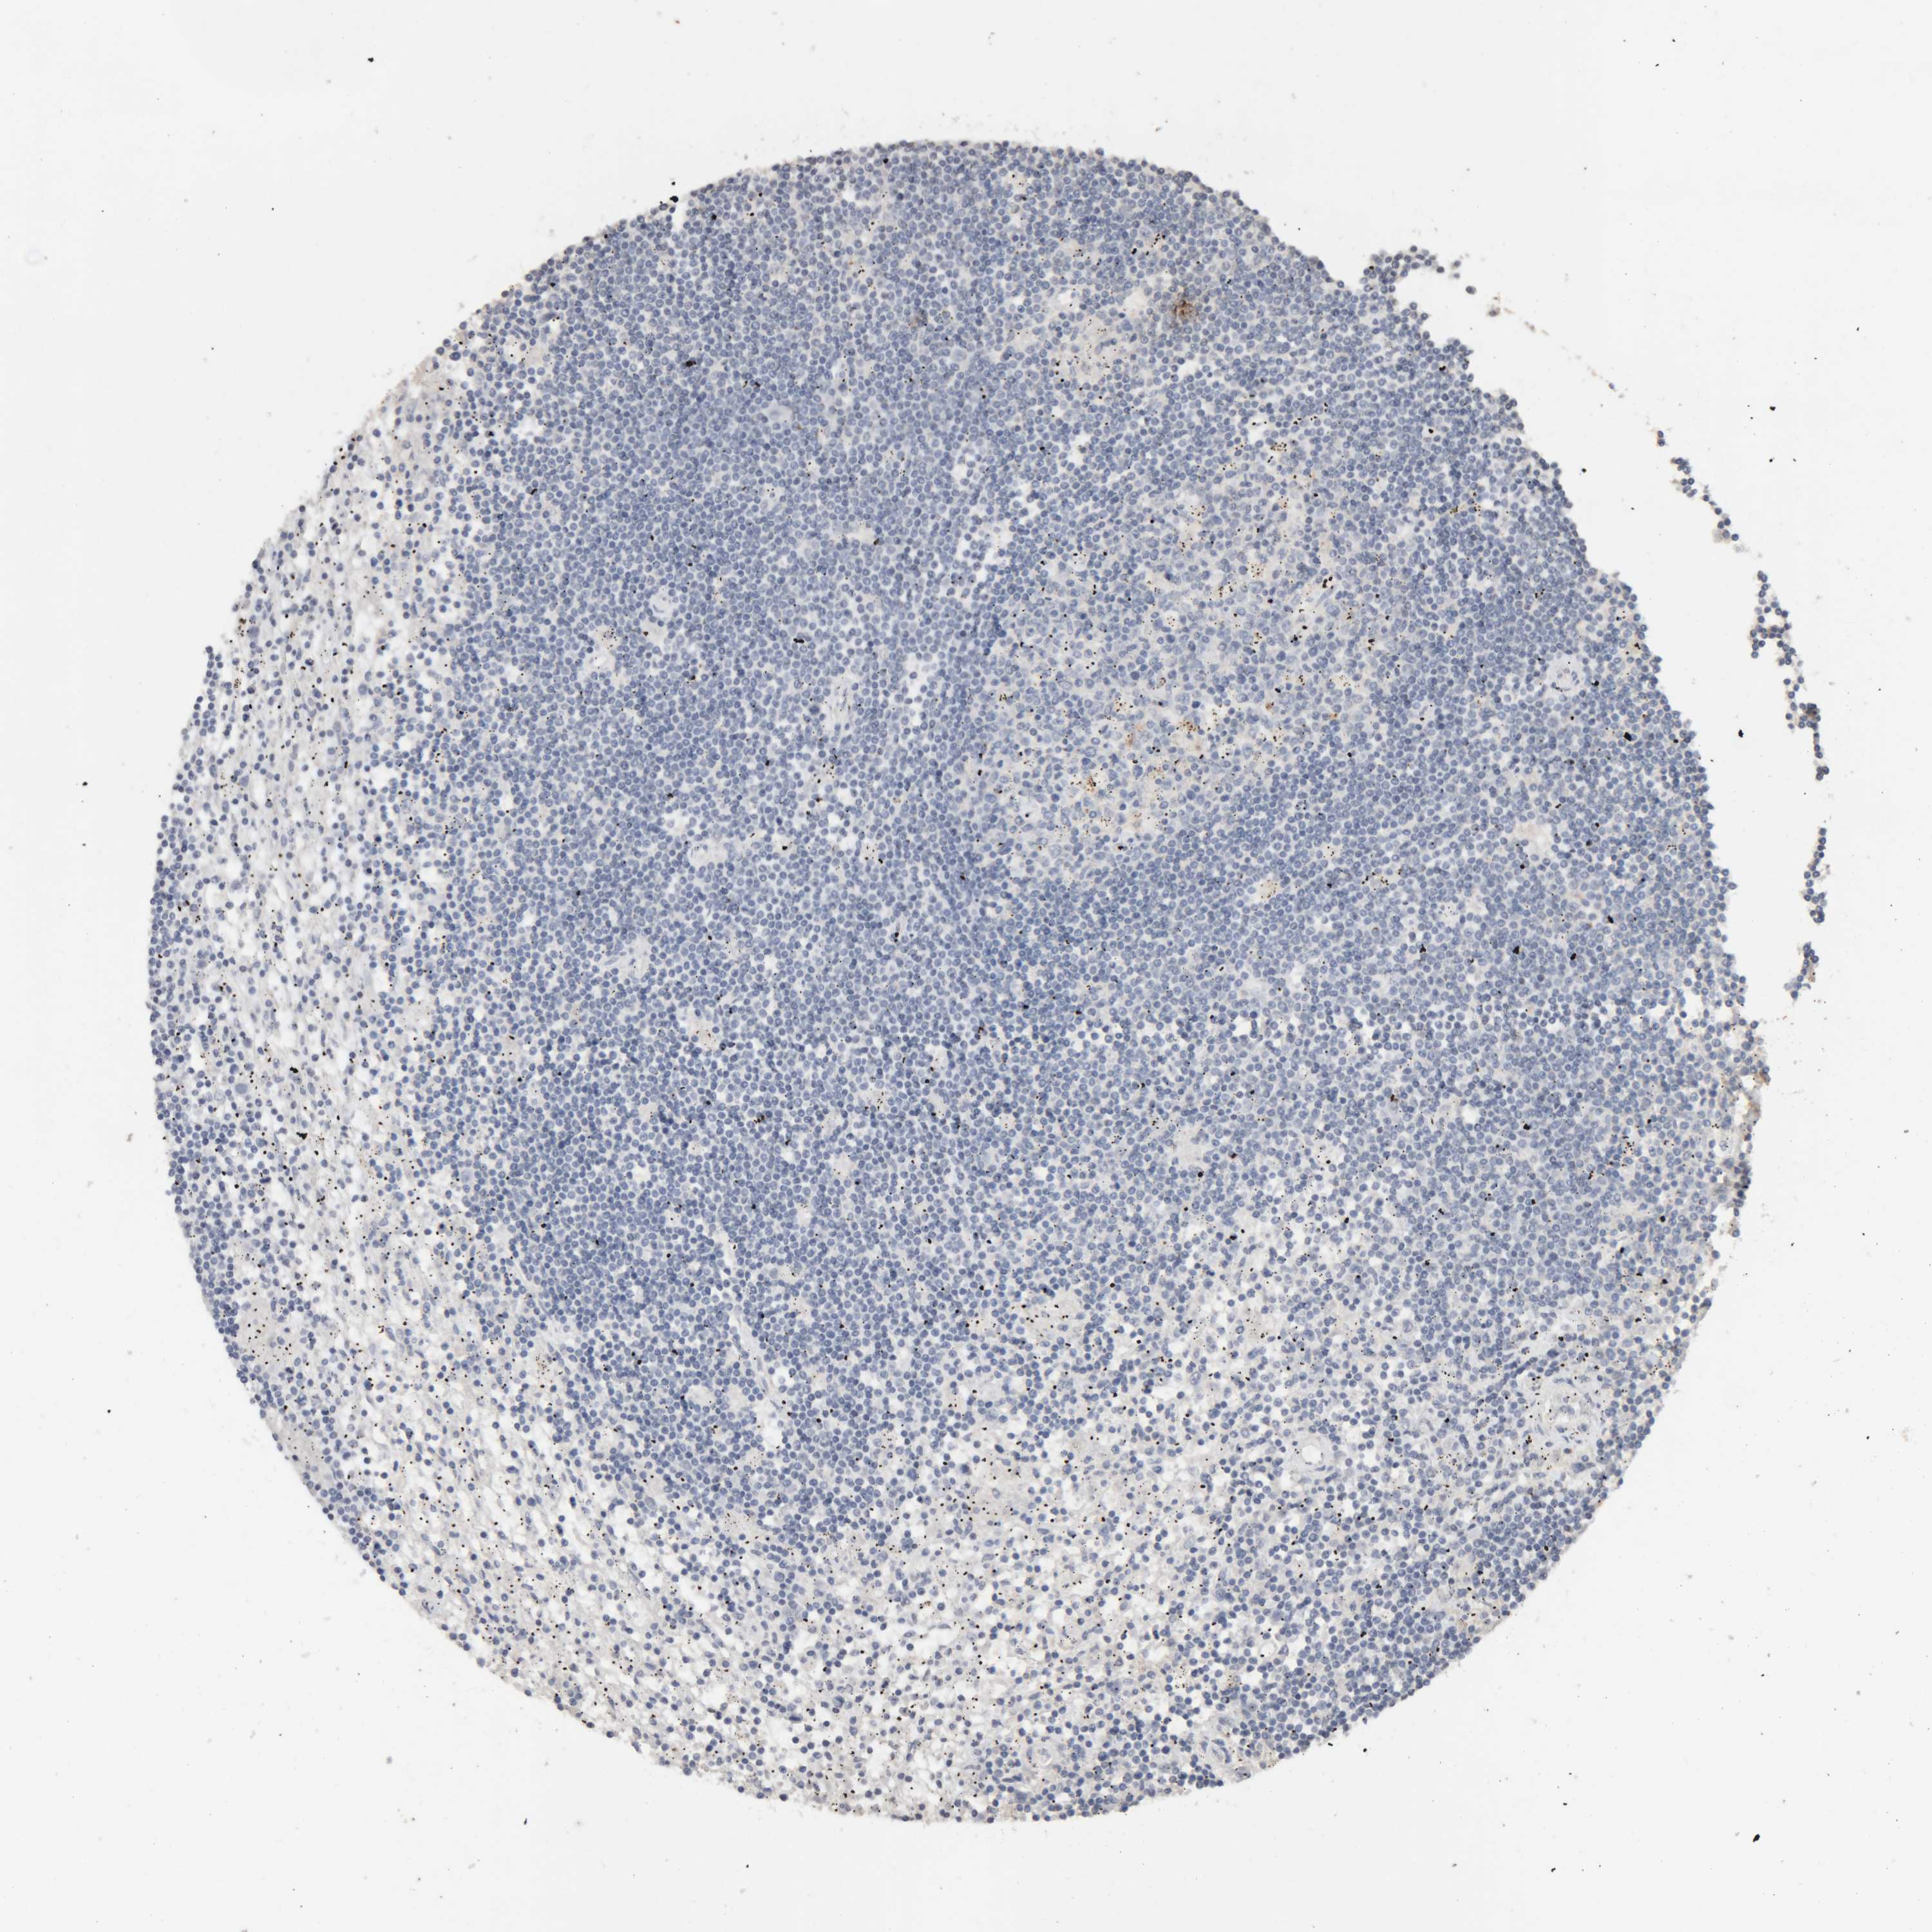

CANCER LYMPHOMA Show tissue menu

LYMPHOMA - Protein expressioni

A mouse-over function shows sample information and annotation data. Click on an image to view it in a full screen mode. Samples can be filtered based on level of antibody staining by selecting one or several of the following categories: high, medium, low and not detected. The assay and annotation is described here.

Antibody stainingi

Antibody staining in the annotated cell types in the current human tissue is reported as not detected, low, medium, or high, based on conventional immunohistochemistry profiling in selected tissues. This score is based on the combination of the staining intensity and fraction of stained cells.

Each image is clickable and will lead to virtual microscopy that enables deeper exploration of all samples and also displays staining intensity scores, fraction scores and subcellular localization as well as patient and tissue information for each sample.

Antibody HPA005554

Antibody CAB025183

Staining

High

Medium

Low

Not detected

Intensity

Strong

Moderate

Weak

Negative

Quantity

>75%

75%-25%

<25%

None

Location

Nuclear

Cytoplasmic/membranous

Cytoplasmic/membranous,nuclear

Hodgkin's disease, NOS

Malignant lymphoma, non-Hodgkin's type, High grade

Malignant lymphoma, non-Hodgkin's type, Low grade